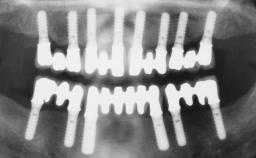

A 68-year-old, completely edentulous male patient presented for evaluation and treatment options. He reported excellent general health and was taking no regular medication. He had been edentulous for approximately 12 years, having lost his teeth to periodontal disease and dental caries. The patient’s chief complaint was incompetent function. His secondary concerns included his appearance and the desire for a predictable outcome. He attributed his reduced functional capacity to his lower complete denture, which he described as poor. He was particularly concerned with the denture’s instability and poor fit. In general terms, he was satisfied with the maxillary complete prosthesis. The maxillary prosthesis was characterized by adequate retention, stability, and support, although the fit was considered less than ideal.